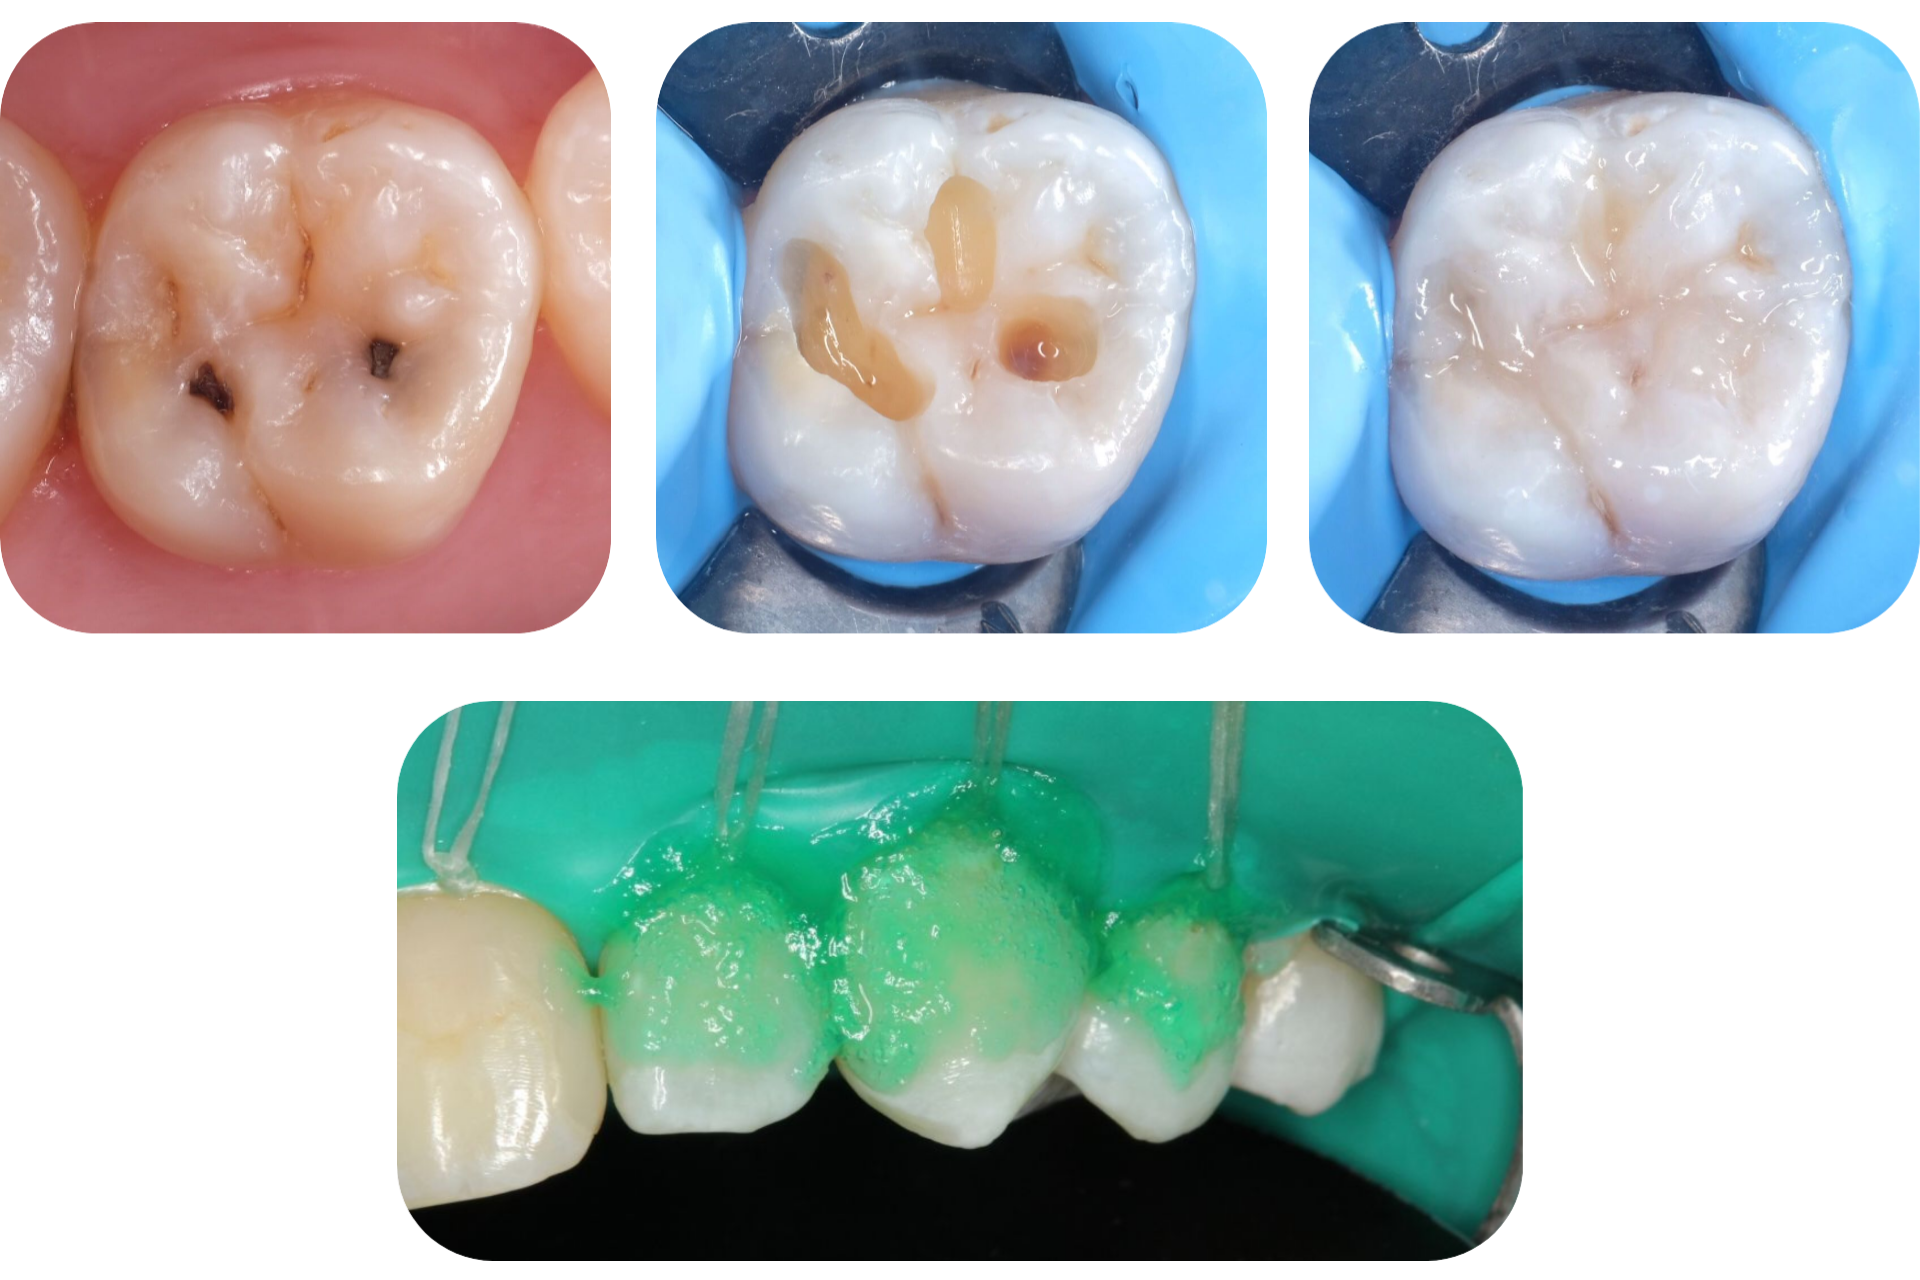

Кариес

Кариес представляет собой повреждение дентина и эмали с образованием дефекта в виде кариозной полости или по-простому «дырке» в зубе.

Методы лечения:

1. Лечение кариеса c пломбой световой полимеризации.

Лечение путем высверливания кариозной полости и постановки пломбы из светоотверждаемых композитных материалов.

2. Лечение начального кариеса без сверления методом ICON.

Технология Icon (Айкон) – это безболезненное лечение кариеса, не требующее сверления эмали. Процедура проводится с использованием специального минералосодержащего материала, который наносится на зуб, проникает внутрь него и там затвердевает, нейтрализуя воспалительный очаг.

Лечение кариеса на жевательных зубах.

После

До